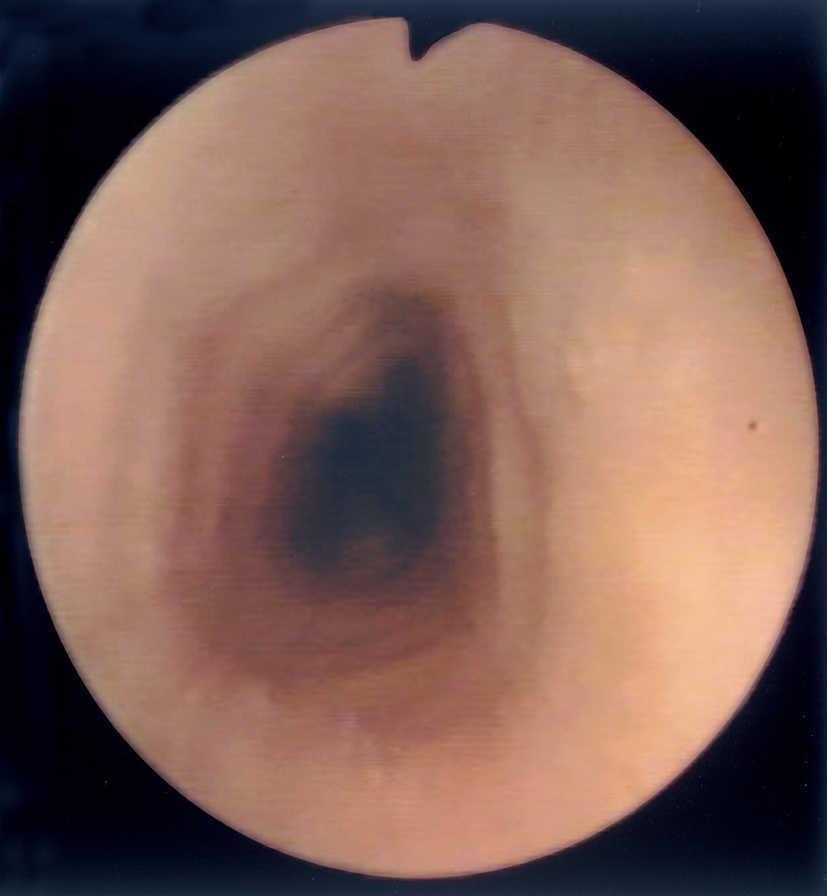

Al estudio endoscópico, en 2 pacientes (18,18 %) se observó una pérdida del patrón circular normal y tendencia a la traquealización (aspecto corrugado y patrón triangular con escasa insuflación) (fig. 1). En otros 2 pacientes se observaron lesiones puntiformes de aspecto blanquecino que correspondieron a acumulaciones de eosinófilos en el estudio histológico (figs. 2 y 3) y en un paciente se observó discreto prolapso cardial. En los otros 6 pacientes los resultados macroscópicos eran normales.

Figura 2. Punteado blanquecino visible en el estudio endoscópico en uno de nuestros pacientes afectados de esofagitis eosinofílica.

En cuanto a los hallazgos endoscópicos pueden ir desde un aspecto de la mucosa esofágica estrictamente normal a diferentes patrones de alteración endoscópica. Se ha descrito la existencia de imágenes erosivas longitudinales, granularidad, pérdida del patrón vascular, estenosis focales6, estenosis de larga extensión ("esófago de pequeño calibre")17 y fragilidad mucosa de fácil erosión al contacto con el endoscopio (denominado como crêpe paper esophagus)18. Pero el patrón que se ha comunicado con más frecuencia es el de traquealización esofágica, denominado de este modo por la presencia de imágenes de anillos transversales consecutivos que recuerdan el aspecto "corrugado" de la tráquea y que corresponderían a contracciones intermitentes de la musculatura circular esofágica19. Otra imagen bastante característica en estos pacientes es un punteado blanquecino que semeja el aspecto de candidiasis esofágica y que corresponde a acumulaciones o microabscesos constituidos por eosinófilos que protruyen sobre la superficie mucosa, como se demuestra por el estudio anatomopatológico20,21. En dos de nuestros pacientes se demostró este hallazgo.